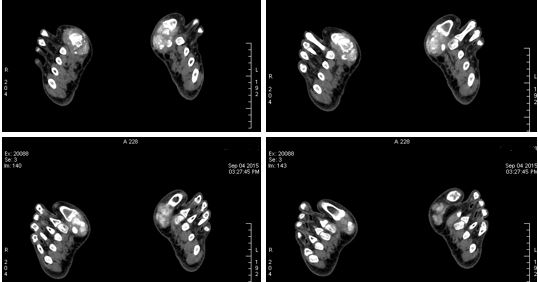

70keV单能图像用调色板直接叠加伪彩

双阈值VOI在尿酸基图像双阈值VOI生成伪彩图,不同物质用不同颜色表达。本例病变,红色代表痛风结节,夹杂蓝色代表痛风内合并的钙化,绿色代表肌肉软组织。

• 尿酸基图以及散点图上,明显的痛风结节与正常的肌肉软组织可以区分。

• 伪彩图像直观的表达病变,有时候更有利于寻找病灶。